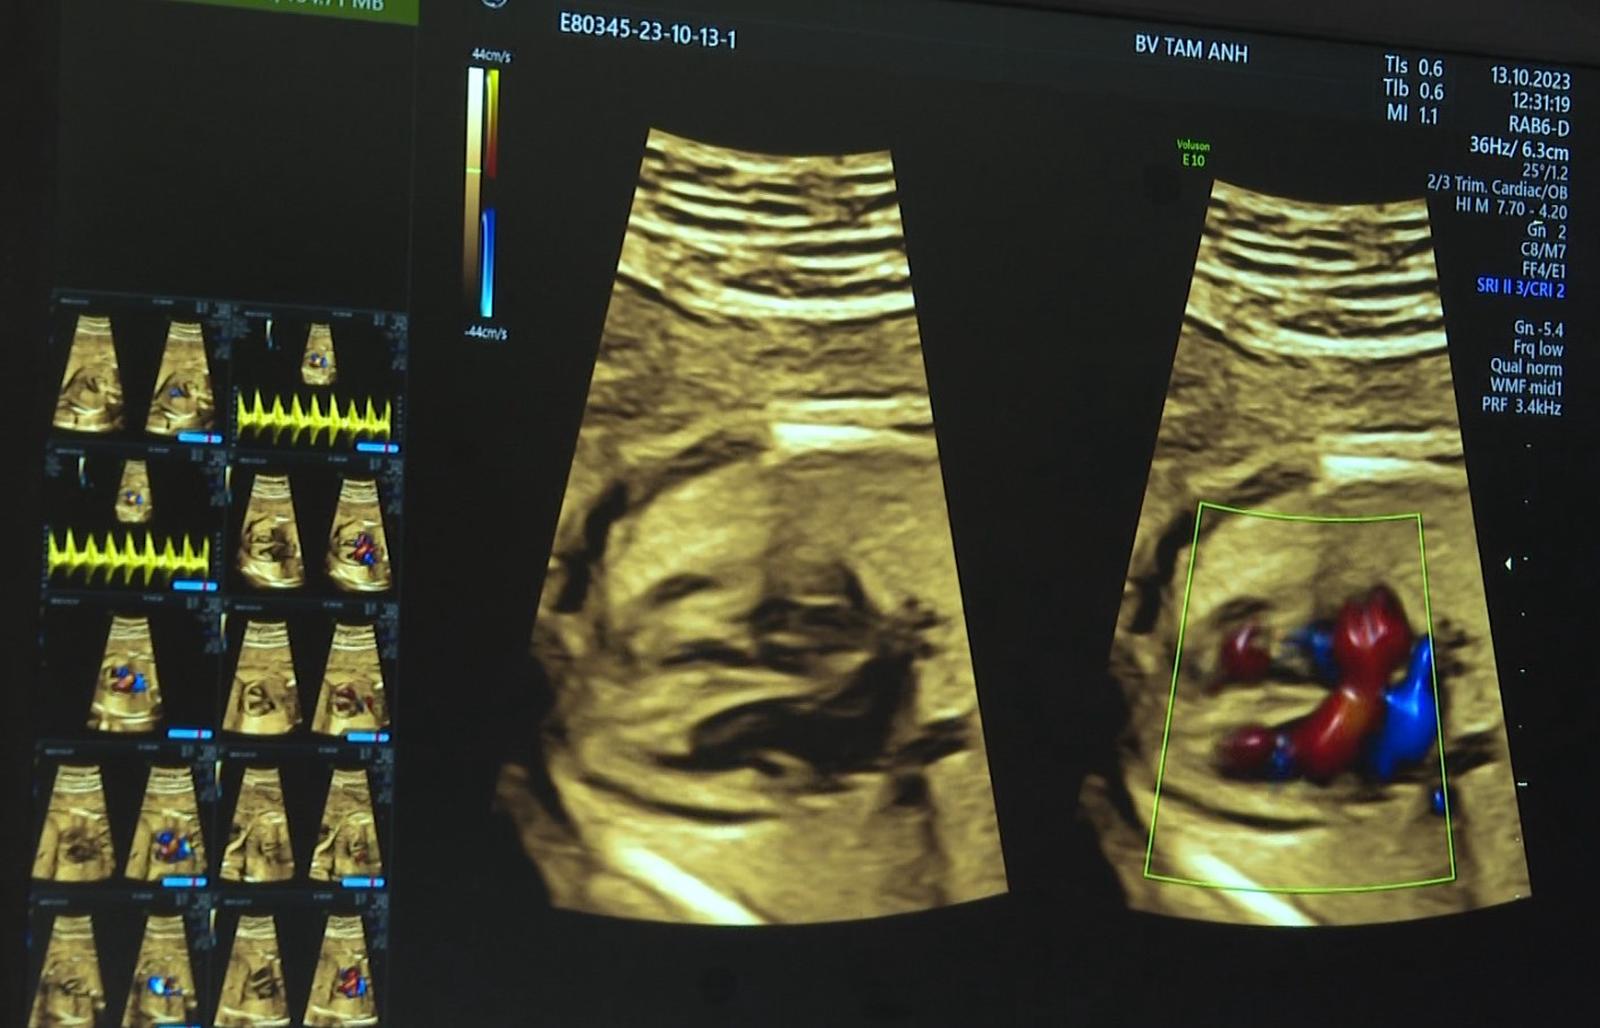

Bệnh viện Đa khoa Tâm Anh trang bị máy siêu âm Voluson E10 của GE Healthcare với phần mềm bản quyền ứng dụng trí tuệ nhân tạo (AI) kết hợp màn hình cảm ứng đa nhiệm công nghệ X-touch dựng hình cấu trúc tim từ bào thai nhỏ như đồng xu trong không gian 4 chiều cực kỳ rõ nét. Máy tự động phân tách từng mạch máu, giúp bác sĩ thuận tiện đánh giá và phát hiện các bất thường. Tất cả chỉ trong một nút bấm, cho kết quả chính xác vượt trội, rút ngắn 70% thời gian chẩn đoán.

Siêu âm cấu trúc tim thai được phân tích bởi công nghệ AI

Siêu "thuật toán" AI trong máy siêu âm tim GE Vivid E95 tự động nhận diện vùng quan tâm (ROI) giúp bác sĩ tính toán phân suất tống máu (EF), đánh giá chức năng tim, nhận diện bất thường và đo đạc cấu trúc tim hoàn toàn tự động, nhanh chóng chỉ với một nút bấm. Công nghệ AI kết hợp bộ đầu dò siêu âm tim 8 kích cỡ từ sơ sinh đến người lớn giúp chẩn đoán chính xác hơn, rút ngắn thời gian, đặc biệt tối ưu khi siêu âm tim cho trẻ sơ sinh và trẻ nhỏ.